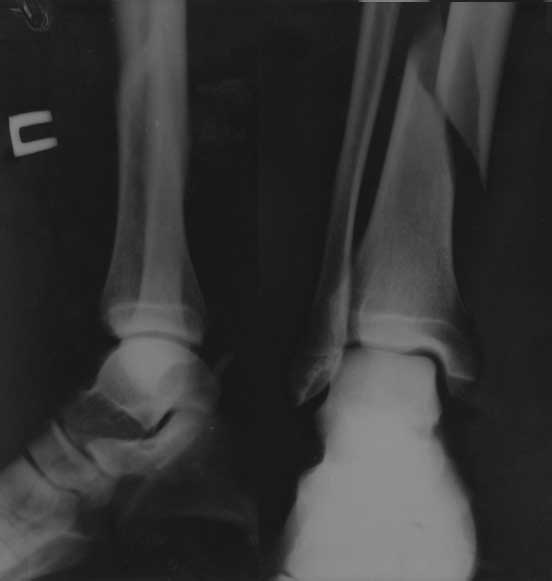

Re: Повторный перелом н/3 большеберцовой кости с наличием металлофиксаторов

Первичный рентген